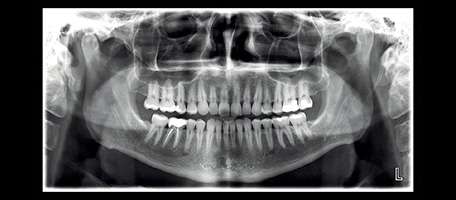

Digitale Volumentomographie (DVT) ist eine Röntgen- Bildgebungstechnologie, bei der auf einer Kreisbahn einzelne Projektionsaufnahmen eines Patienten aus unterschiedlichen Winkeln aufgenommen werden. Ein volumetrisches 3D-Bild der abgebildeten Region wird aus diesen 2D-Projektionen errechnet. Die daraus resultierende isometrische Ortsauflösung im Volumen kann mit unserem fortschrittlichen Bildbearbeitungsprogramm aus jedem Winkel in der axialen, koronalen und sagittalen Querschnittsebene betrachtet werden.